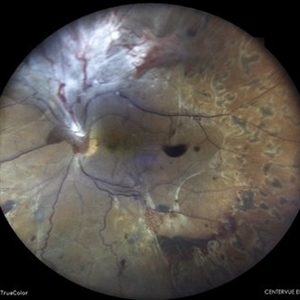

TRACTIONAL RETINAL DETACHMENT IN A CASE OF VASCULITIS

MONTAGE OF A 27 YEAR OLD MALE WITH TREACTIONAL RETINAL DETACHMENT IN A CASE OF VASCULITIS

Photographer: Dr. Akansha Sharma-Retina Foundation, Ahmedabad

Condition/keywords: pan-retinal photocoagulation (PRP), tractional retinal detachment, VASCULITIS